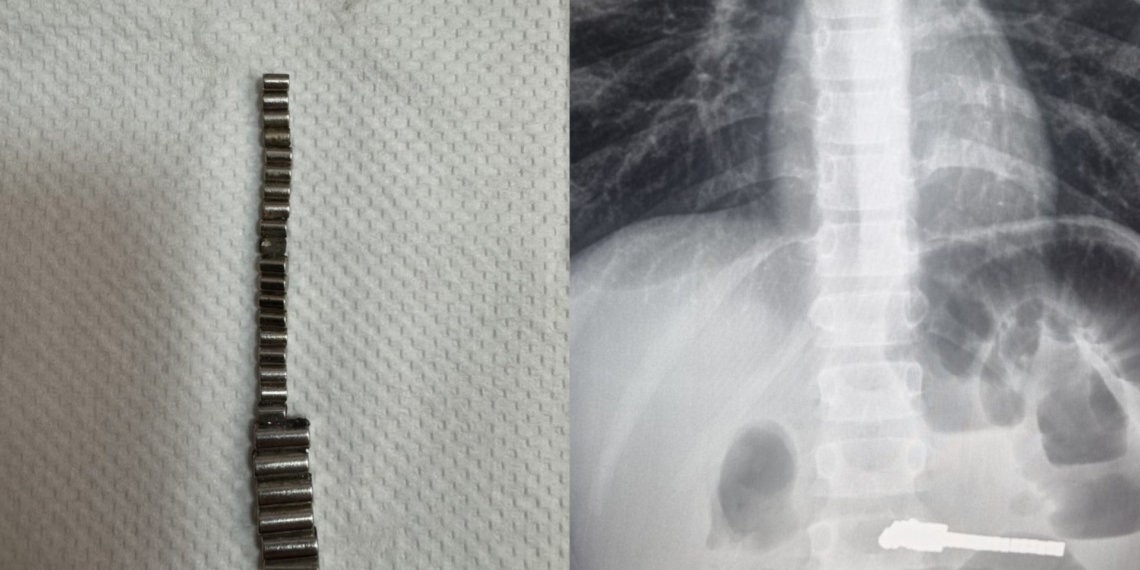

Оказалось, что в кишечнике ребёнка находились инородные предметы. Врачи больницы провели оперативное хирургическое вмешательство и извлекли из желудка пациента 25 магнитов. Длительное нахождение подобных предметов в ЖКТ привело к серьёзным осложнениям, но, к счастью, сейчас жизни ребёнка ничего не угрожает. Операция прошла успешно.